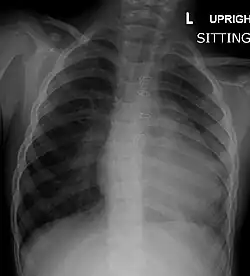

Chest radiograph

Before more sophisticated techniques became available, chest X-ray was the definitive method of diagnosis. The abnormal "coeur-en-sabot" (boot-like) appearance of a heart with tetralogy of Fallot is classically visible via chest X-ray, although most infants with tetralogy may not show this finding.[50] The boot like shape is due to the right ventricular hypertrophy present in TOF. Lung fields are often dark (absence of interstitial lung markings) due to decreased pulmonary blood flow.[51]: 171–172